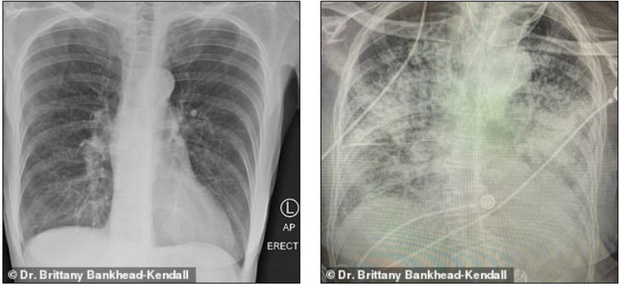

Bác sĩ phẫu thuật Brittany Bankhead-Kendall ở Trung tâm Khoa học Sức khỏe Đại học Kỹ thuật Texas (Mỹ) mới đây trưng ra 3 tấm phim chụp X-quang: Một của bệnh nhân khỏe mạnh, một của người hút thuốc, và một của bệnh nhân Covid-19.

Phim của người khỏe mạnh có nhiều khoảng đen, cho thấy họ có thể hít vào đủ lượng oxy cần thiết. Phim chụp phổi người hút thuốc thì có nhiều khoảng mờ, còn của bệnh nhân Covid-19 thì gần như trắng xóa.

Những khoảng mờ trên phim chụp phổi thường là chỉ dấu của dịch lỏng, vi khuẩn, hoặc tổn thương và vết sẹo.

Bác sĩ Kendall đánh giá, phổi của các bệnh nhân trải qua Covid-19 tệ hại hơn bất cứ người nghiện thuốc lá nào mà bà từng biết.